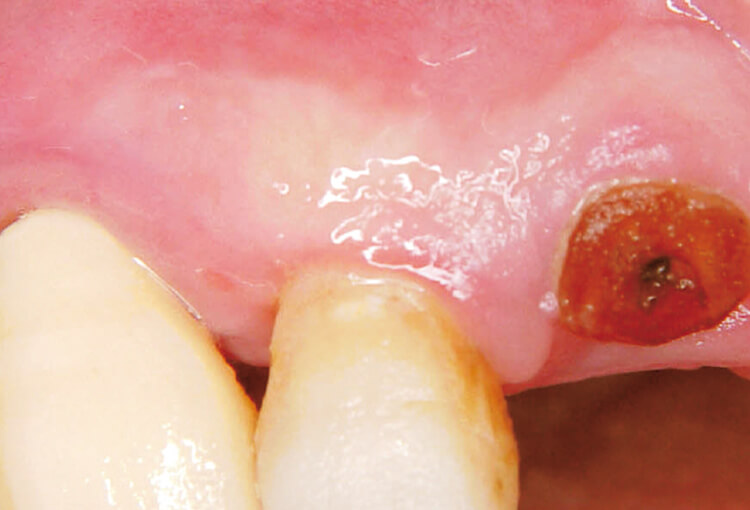

症例2 歯周膿瘍(下顎左側中切歯) 70歳 男性

レーザー照射を行った後、TCPSを瘻孔から溢れ出るように適用すると早期に炎症が改善された。その際、使用時の疼痛はなかった(図7~9)。

図7 症例2 初診時- ・動揺++

- ・排膿++

図8 レーザー+TCPS- ・Er:YAGレーザー(20pps40mj)にて注水下、無麻酔でポケット内照射

- ・瘻孔から溢れ出るようにTCPSを適用

図9 術後1週間- ・炎症症状は消失